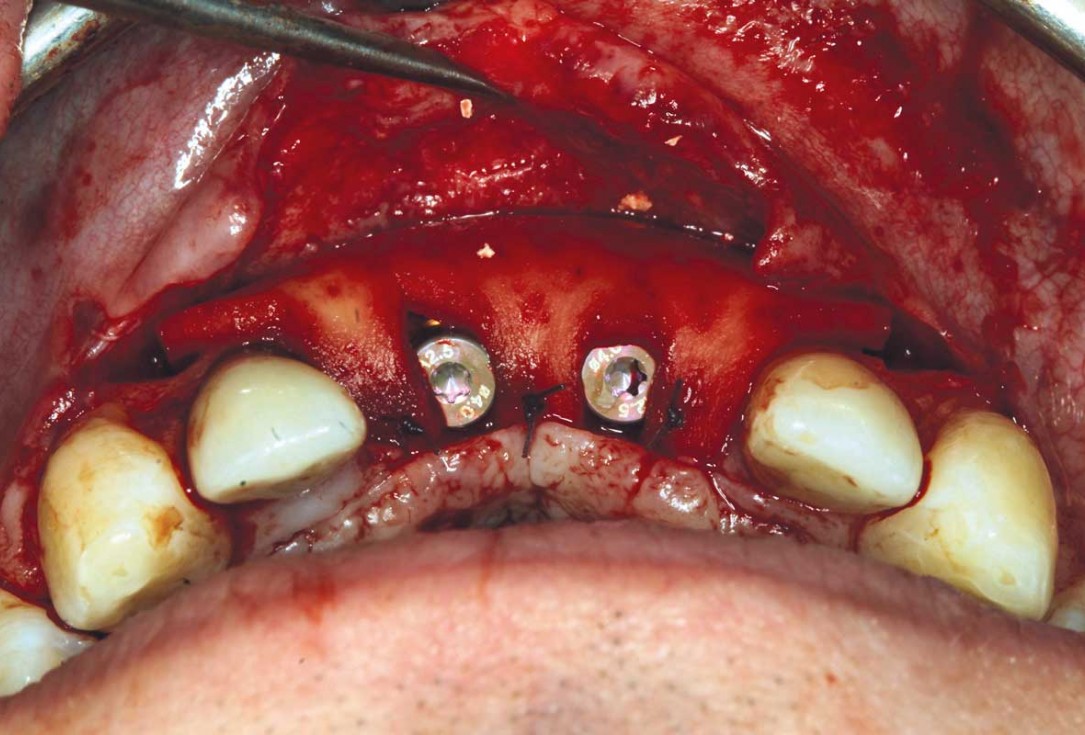

17/26 - Insertion of two Straumann BLX implants 3.75 x 14 mm / 3.75 x 12 mm

Ridge augmentation in the maxilla with maxgraft® bonebuilder in the aesthetic zone - Dr. M. Kristensen